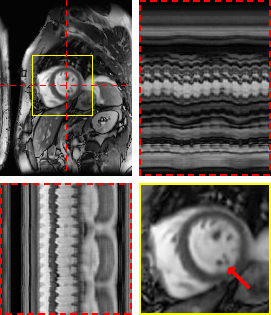

Figure 4: Exemplary real-time cine reconstructions. Each sub-figure illustrates an end-diastolic frame, temporal profiles, and a close-up on the heart. Red arrows show an area where differences in image sharpness are particularly apparent.

Refer to caption

(a) M-DIP

(b) LR-DIP

(c) L+S

Figure 5: Exemplary free-breathing single-shot LGE reconstructions. Each sub-figure illustrates one frame, temporal profiles, and a close-up of the heart. Red arrows show details that are better visible in M-DIP compared to LR-DIP.

In the second study, we reconstructed prospectively undersampled free-breathing real-time cine data in clinical patients and reconstructed them using M-DIP, LR-DIP, L+S, and a recently proposed supervised learning method (CineVN). As no ground truth is available, a reader study was performed by two experienced readers.

In terms of noise and artifacts, M-DIP and CineVN performed the best, while the scores for LR-DIP were insignificantly lower. L+S received the lowest scores, exhibiting high levels of noise in the reconstructions. In terms of image sharpness, M-DIP reconstructions received significantly higher scores, while LR-DIP received the lowest scores. Visual inspection again reveals blurring in the LR-DIP reconstructions mainly around the myocardium, suggesting a limitation of the low-rank model in the presence of complex motion over multiple respiratory and cardiac cycles in a large field of view, as seen in Figure 4. The M-DIP framework in contrast allows generating a high-resolution template image for each frame which is then deformed to the respective motion state. The high scores for noise and artifacts in M-DIP and LR-DIP furthermore highlight the implicit capability of DIP-based methods to generate natural-looking images [ulyanov2018deep].

Notably, M-DIP significantly outperformed CineVN in terms of image sharpness, even though it did not benefit from training data. Since acquiring fully-sampled training data for real-time cine is infeasible, CineVN was exclusively trained on breath-held segmented acquisitions, which may have limited its performance on free-breathing real-time data. In contrast, M-DIP is unsupervised and directly learns the physiological motion and content variations from the undersampled data itself.